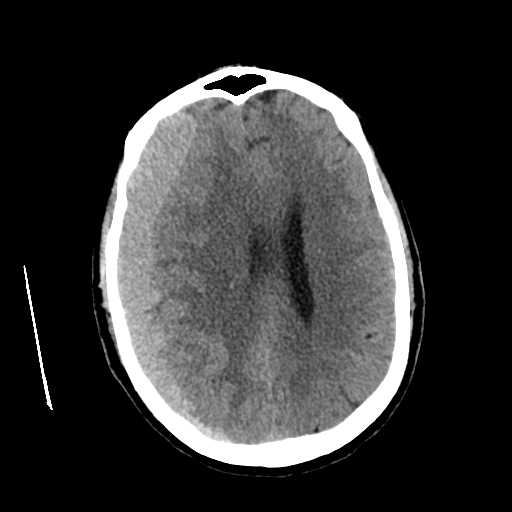

Se realiza tomografía cerebral simple de urgencia, la cual demuestra colección extraaxial hemisférica derecha de localización frontoparietal, con morfología predominantemente semilunar, adquiriendo en algunas áreas aspecto lenticular. La colección presenta densidad compatible con sangre aguda (aproximadamente 50 UH), con espesor máximo de 25 mm y volumen estimado de 100 cc.

La lesión condiciona importante efecto de masa, evidenciado por:

- Aplanamiento de surcos corticales derechos

- Alteración leve en la diferenciación sustancia gris-blanca por edema compresivo

- Desviación de la línea media hacia la izquierda de aproximadamente 10 mm

- Reducción de la amplitud del ventrículo lateral derecho

- Compresión leve del mesencéfalo

No se identifican otras lesiones hemorrágicas intraparenquimatosas ni signos de infarto agudo asociados en el momento del estudio.

Los hallazgos son compatibles con hematoma extraaxial derecho (subdural agudo vs epidural atípico), con repercusión significativa sobre estructuras intracraneales, constituyendo una urgencia neuroquirúrgica.